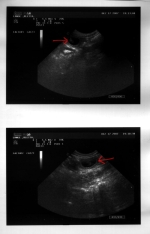

Und tatsächlich sehen wir auf dem Ultraschall deutlich mehrere Welpen - Bletta ist trächtig!

Jetzt beginnt die Zeit, zu der sich die Welpen in der Gebärmutter einnisten und ihre Organe ausbilden. Bletta läßt sich noch nichts weiter anmerken, aber wenn sie auf dem Rücken liegt, ist ihr Bauch schon nicht mehr so flach wie vorher. Wir sind sehr zuversichtlich, daß dieses Mal alles gut gehen wird.

Das Ultraschallbild vom 17.12.2007